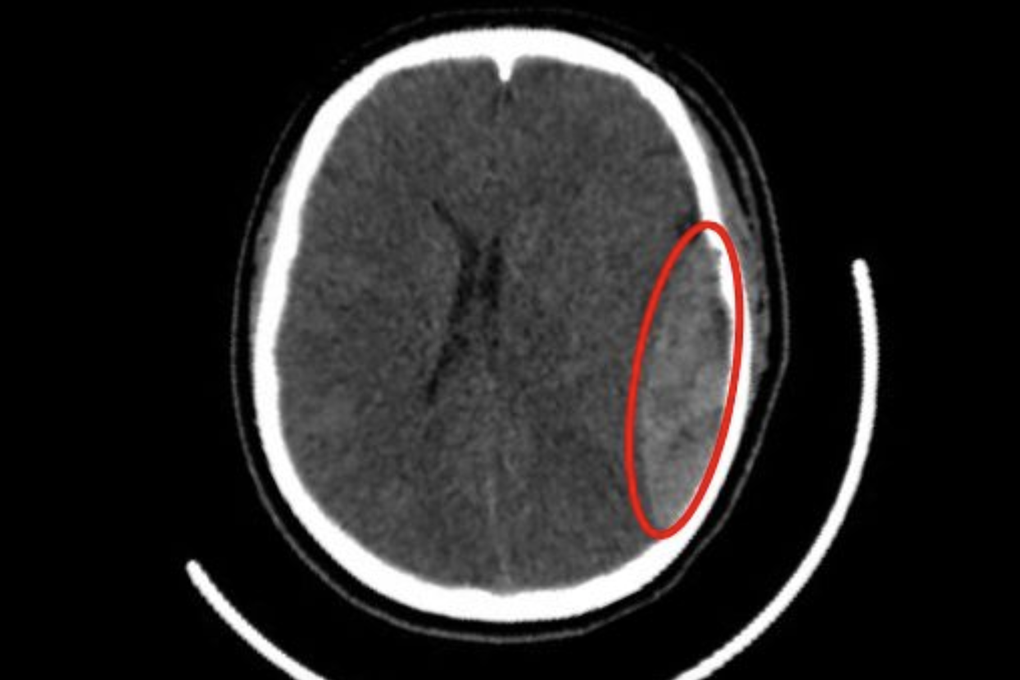

Đó là trường hợp của anh H. (28 tuổi, ngụ tỉnh Tây Ninh). Cú kẹp cực mạnh từ cửa thang máy trong quá trình làm việc khiến nam công nhân đổ gục. Phát hiện sự việc, đồng nghiệp của anh đã giải cứu và đưa nạn nhân đến bệnh viện ngay.Tại khoa Cấp cứu, các bác sĩ tiếp nhận nam bệnh nhân trong tình trạng nguy kịch, suy hô hấp, suy tuần hoàn nghiêm trọng, kèm những vết thương dập, hở phức tạp vùng đầu - cổ làm ảnh hưởng đến hô hấp. Trong đó, vành tai trái của bệnh nhân gần như đứt lìa.Ngay lập tức, ê-k...